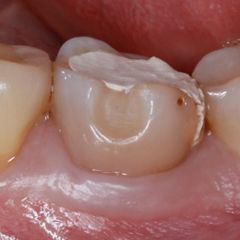

The patient’s individual treatment plan consisted of professional oral hygiene, therapeutic and endodontic treatment, surgery and final prosthetic implementation. During treatment based on the general treatment plan, tooth #36 was found to have secondary caries under the composite restoration (Fig. 1). Deep subgingival destruction was observed in the distal interproximal area (Fig. 2). Surgical lengthening of the crown was difficult due to the exposed furcation; therefore, a prosthetic crown was not a recommended treatment option for this tooth. Based on all information, the dental team decided to extract #36 and perform an immediate implant placement.